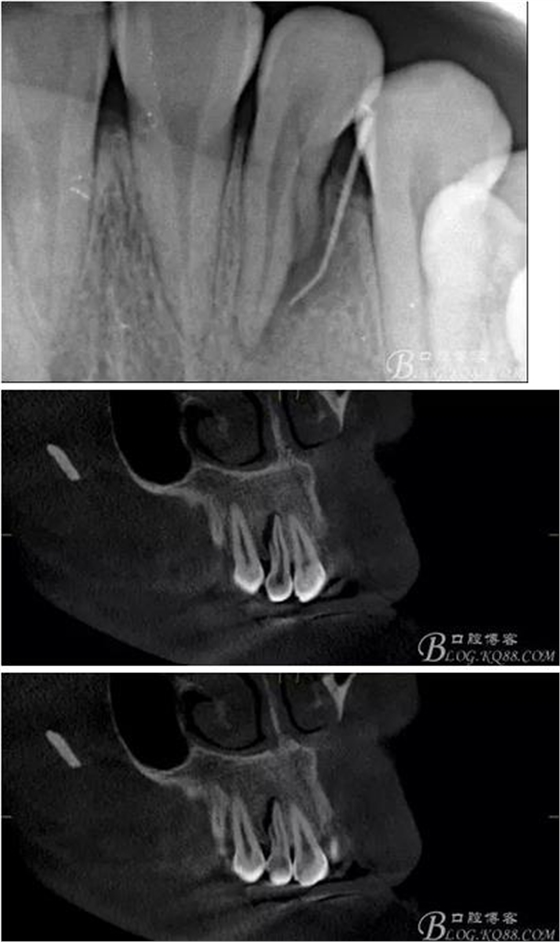

(1)檢查:12唇側(cè)牙齦可見竇道,牙體顏色較鄰牙暗,無光澤,形態(tài)完整無缺損,唇側(cè)及近遠(yuǎn)中向未提及牙周袋。腭側(cè)齦緣輕度紅腫,舌側(cè)窩可探及裂溝,可見浸墨狀痕跡,沿裂溝舌側(cè)探診牙周袋深大于11mm,除患牙外全口牙周狀況良好,為探及牙周袋,牙齦色粉紅。邊緣菲薄,質(zhì)地堅(jiān)韌。12冷熱診無反應(yīng),叩診(+-),無明顯松動(dòng),無咬合創(chuàng)傷。12根尖x線片示,根管中三分之一中可見一斜向線樣透射影像根尖區(qū)及遠(yuǎn)中根三分之一可見低密度透射暗影,錐形束CT示12根尖區(qū)唇腭向骨吸收已穿通,根面溝達(dá)根中三分之一卷曲分出另一牙根,再未見其他明顯的根管系統(tǒng)。

(6)復(fù)診:原暫封材料再位,牙周無明顯異常與不適,常規(guī)清潔根管,H銼清除根管內(nèi)維他,次氯酸鈉終末消毒,干燥根管,單尖測(cè)壓發(fā)充填根管,術(shù)后拍片到位。